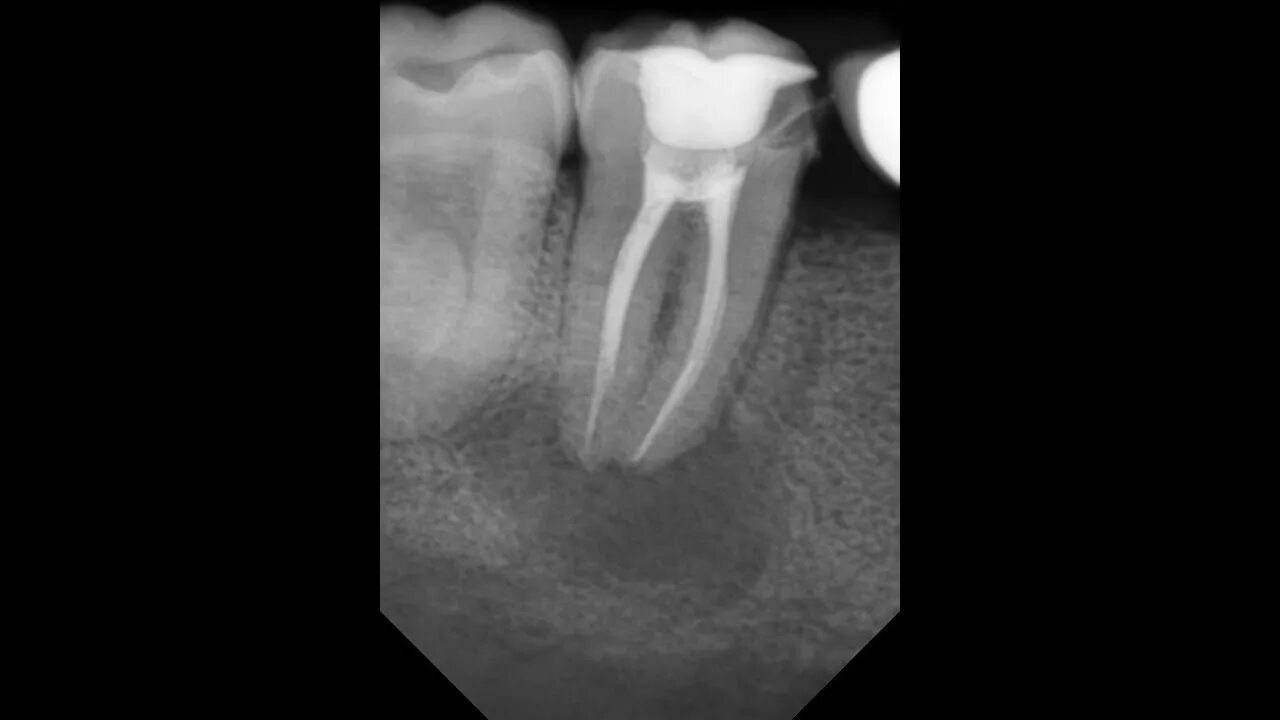

Пломбирование перфорации